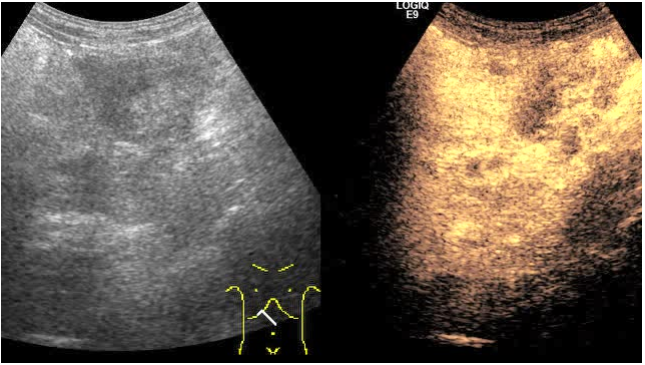

超声检查所见:

超声所见:

其他检查: